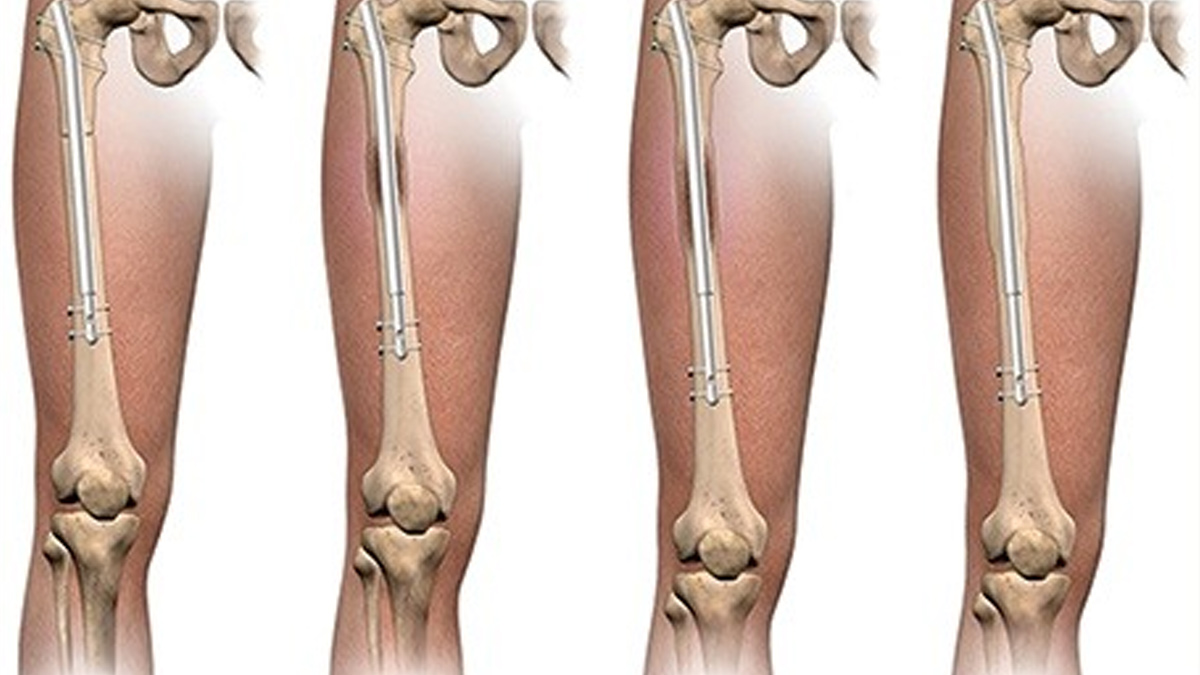

- The bone is allowed to rest after surgery taking a couple of days. Then the lengthening starts, and the rate is generally about 1 mm/day.

- New bone tissue grows to replace the gap that is created as the bone gradually separates.

- This period may take several weeks or months, and in the course of this period, a patient may visit the doctor frequently to check up and perform physical therapy.

After the target length, a period of healing ensues in which a new bone hardens and becomes as strong as the old one. All in all, this entire process may last months and has to be done with patience and caution.